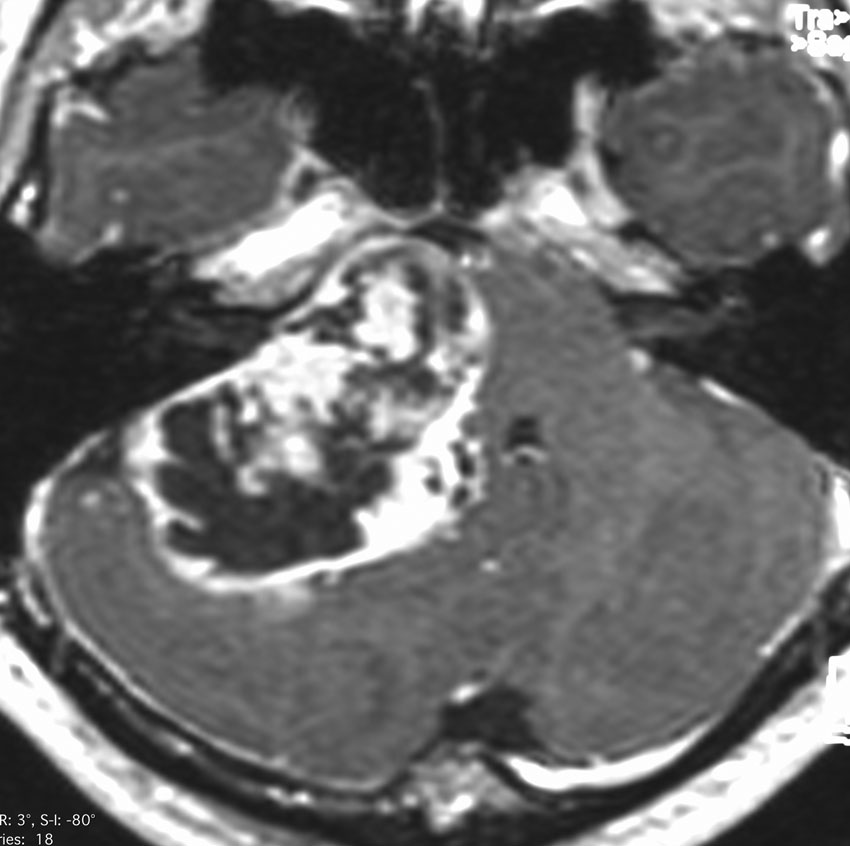

症例:小脳延髄角部のもの,聴神経腫瘍と紛らわしいもの

水頭症による頭痛,嘔吐と右聴力低下で発症しました。体側の左側の感覚低下としびれがありましたが,それはbrainstem distortionによるものでした。一見,聴神経腫瘍にみえるのですが,内耳道内に腫瘍がありません。

手術では,脳槽内迷走神経根の一部が腫瘍化したものでした。顔面神経と聴神経との剥離は容易でした。

機能的にも聴神経,舌咽神経,迷走神経は温存できました。

術後しばらくの嚥下障害は改善,迷走神経症状としての咳嗽発作が6年ほどありましたが治りました。